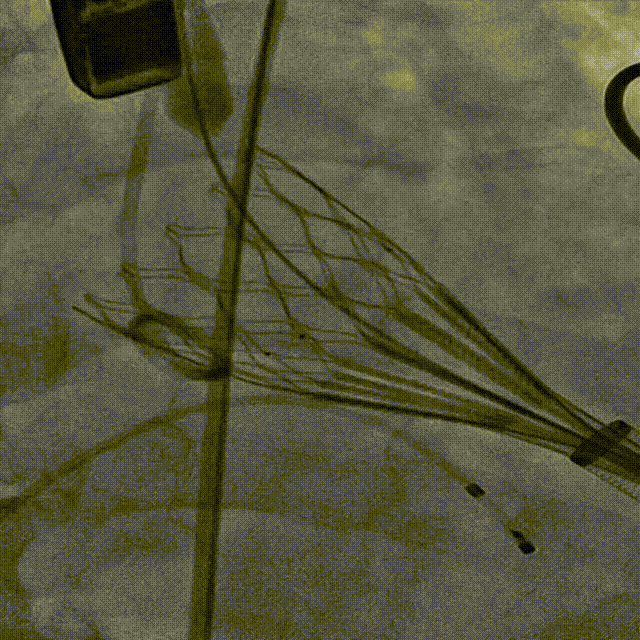

第二次释放

造影观察 瓣膜深度可

稳定脱钩,瓣膜无位移

最终造影,瓣膜位置可,几乎无瓣周漏